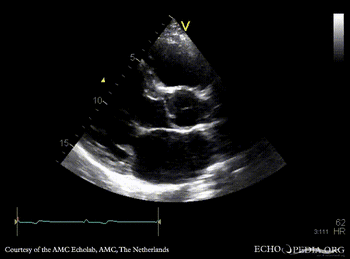

| Marfan Syndrome

| Courtesy of: AMC Echolab, AMC, The Netherlands

| PLAX with Color Doppler: mild mitral regurgitation

PSAX: redundant mitral valve leaflets